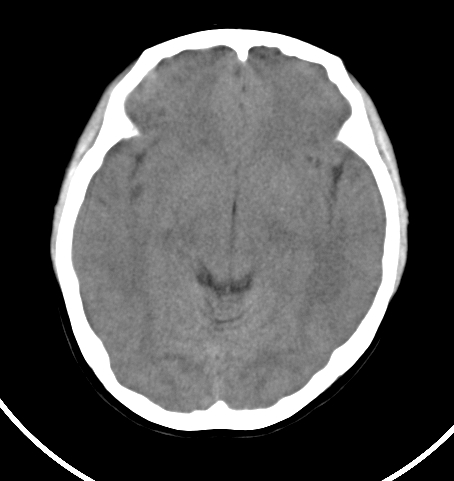

病人女 35岁 自述头晕 头痛

双侧基底节区及右侧丘脑区多发点状钙化,周围未见水肿及占位征象.余未见明显异常.考虑:脑囊虫病<囊虫的退变或死亡期>请结合有无相关病史.

以下是引用苯小孩在2007-4-20 15:47:00的发言:[br]双侧基底节区及右侧丘脑区多发点状钙化,周围未见水肿及占位征象.余未见明显异常.考虑:脑囊虫病<囊虫的退变或死亡期>请结合有无相关病史.

颅内有散在钙化

脑囊虫病理性钙化。